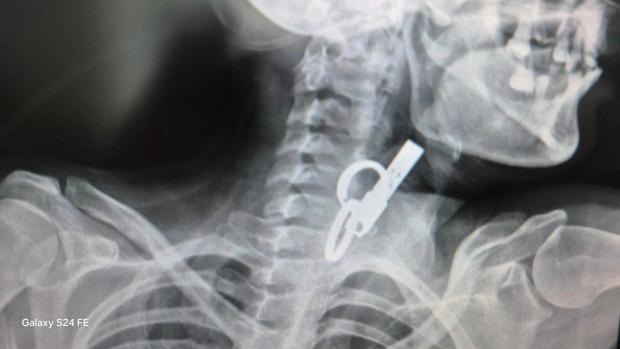

«Це дуже показовий випадок, що нам вдалося її врятувати. Як свідчить практика, переважно такі хворі гинуть. Спочатку ми не могли зрозуміти, що застрягло у стравоході. Це були якісь металеві кільця, які стояли зверху, а далі було ще якесь чужорідне тіло. Я здогадався, що це може бути ключ від дверей і почав його обережно витягувати», – розповів Олександр Садовий.

З’ясувалося, що ключ жінка проковтнула, щоб не віддати його родичам і, щоб вони не мали доступ до її помешкання. Лікар додає, що в обласну лікарню у Тернополі не ризикнули везти пацієнтку, оскільки її вже доставили в стані шоку, то жінку просто б не довезли. Рішення про операцію приймали за лічені хвилини.